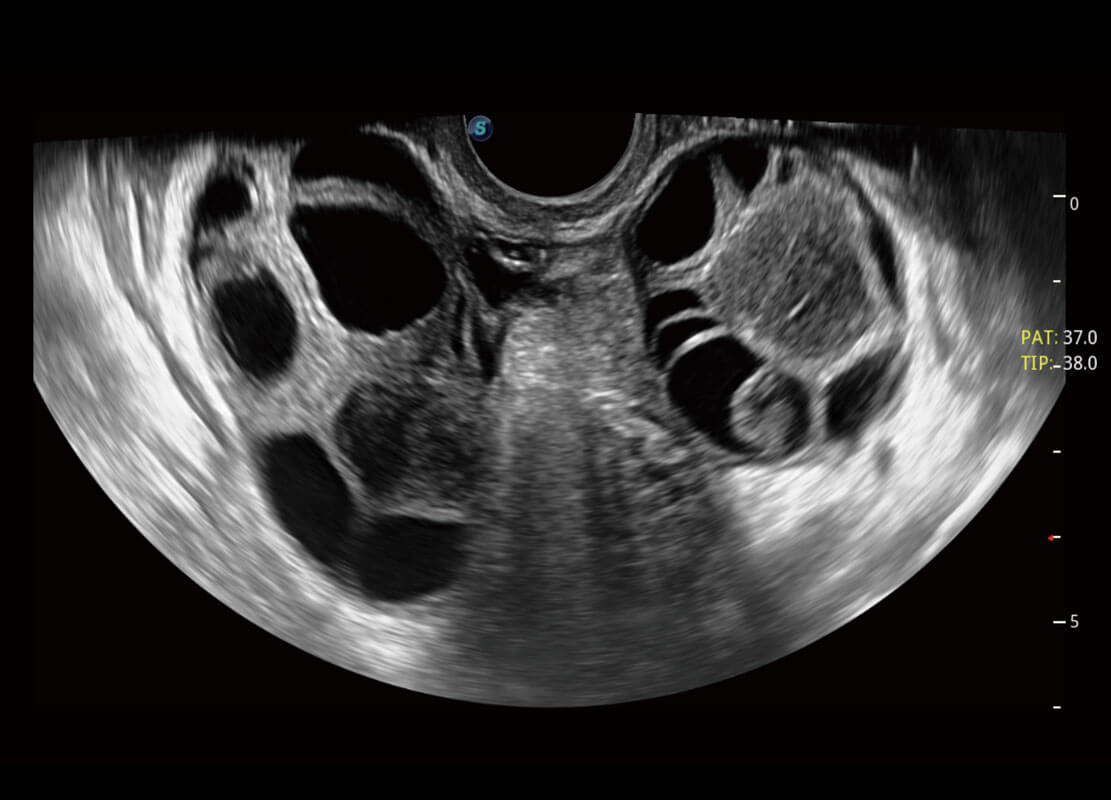

腔内妇科-卵巢